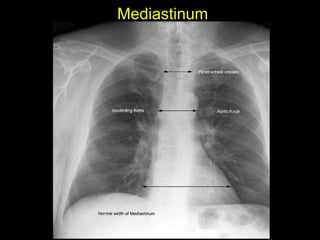

The document discusses the anatomy of the chest x-ray and CT scan by describing the lobes of the lungs and their locations. It also mentions the heart, mediastinum, hilum, and ribs. Several axial, coronal, and sagittal CT images are included with labels pointing out structures like the trachea, bronchi, lobes of the lungs, and fissures. In summary, the document provides an overview of lung and chest anatomy as seen on x-rays and CT scans through text descriptions and labeled medical images.